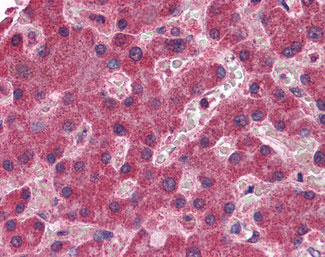

Anti-MGLL antibody IHC of human liver. |